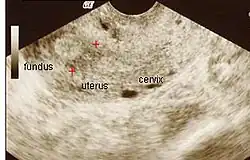

![]() | |

| Ultrasound view. | |

The history of a pregnancy event followed by a D&C leading to secondary amenorrhea or hypomenorrhea is typical. Hysteroscopy is the gold standard for diagnosis.[18] Imaging by sonohysterography or hysterosalpingography will reveal the extent of the scar formation. Ultrasound is not a reliable method of diagnosing Asherman's Syndrome. Hormone studies show normal levels consistent with reproductive function.